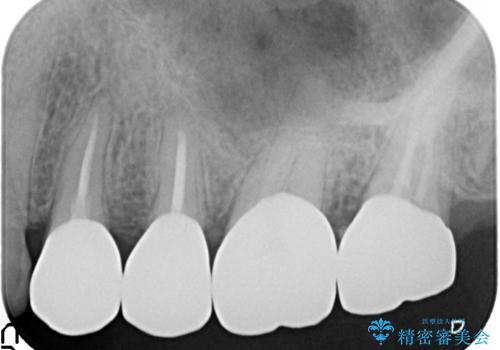

放置した虫歯 根管治療 フルジルコニアクラウン

樹脂やクラウン・銀歯の老朽化がみられるため、丁寧に除去を行い根管治療を行ったのち、歯軋り・厚みの少なさを鑑みフルジルコニアクラウンによる補綴を計画します。

- 38万円(仮歯・ファイバーコア・フルジルコニアクラウン×4)費用は治療当時の料金となります